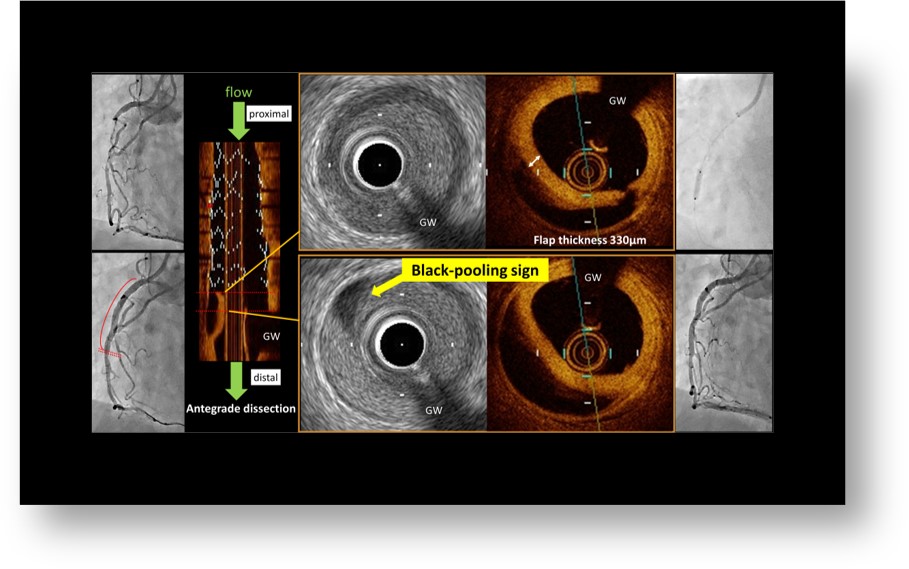

92.

Black-pooling sign: A novel intravascular ultrasound imaging marker that predicts stent edge hematoma growth

Anatol J Cardiol. 2021 Apr;25(4):E15.

doi: 10.14744/AnatolJCardiol.2020.49921.

IVUSにおけるblack-pooling signはステントdistal edgeの血腫増大を予測し得る

Yusuke Oba/大場 祐輔

冠動脈ステント留置における解離や血腫は、ステント遠位側に形成されば場合、順行性の解離となり急性冠閉塞のリスクがある。IVUS評価は有用だが、時にGWアーチファクトによる観察制限など、IVUS上明らかな解離が指摘できない場合がある。IVUSでフラップが観察出来なくても、Black-pooling signを認める場合には、血腫内に生食や造影剤が入り込む順行性解離腔が存在すると考える必要があり、血腫増大をきたし得る重要な所見と考えます。